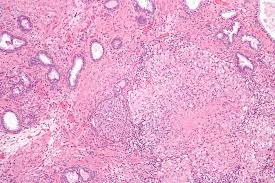

방광염(Bladder Inflammation)은 방광 내막(방광 벽면을 덮고 있는 조직)의 염증을 나타내는 의학적 용어입니다. 방광 내막의 염증은 주로 소변 방출과 관련된 고통과 불편을 유발하며, 종종 소변 통증, 빈발 소변, 혈뇨(소변에 혈액 혹은 혈전 혼합), 저림 통, 소변 불편감 등과 같은 증상을 동반합니다. 방광염은 다양한 원인에 의해 발생할 수 있으며, 원인에 따라 적절한 진단과 치료 절차가 필요합니다.

5. 방광내경 (시스토스코피): 만약 의심스러운 경우, 방광내경 검사가 수행될 수 있습니다. 이 과정에서 유연한 관찰용 관을 통해 방광 내부를 직접 확인하고 염증, 결석, 기타 이상을 시각화합니다.